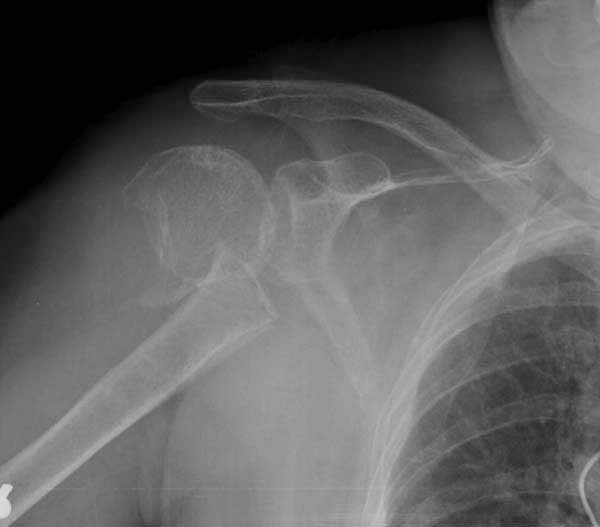

Немного причин, приводящих к вывихам после фиксации переломов проксимального плеча. В результате несоответствия суставной поверхности лопатки и головки плеча из-за потери кости по задней поверхности головки плеча или в задней половине суставной впадины. Или в результате отсутствия мягкотканого покрытия, к которому можно отнести разрывы манжетки или суставной капсулы. А также когда повреждается нерв.

При вывихе плеча редко повреждается лучевой, серединный или локтевой нервы, и поэтому нормальная неврологическая функция на периферии конечности еще не доказательство интактного неврологического статуса. Но повреждения аксиллярного нерва встречаются очень часто, например, во время травмы или ятрогенное - во время неосторожных хирургических манипуляций. Отсутствие чувствительности над дельтовидной мышцой и атрофия покажет повреждение аксиллярного нерва. Потеря функции дельтовидной мышцы приводит к вывиху сустава вниз. Или повреждение n.subspinatus приводит к дисфункцию мышцы, в результате манжетка не может удержать головку.

Набор мелких снимков не отражает истинную картину суставной поверхности лопатки, а также качество репозиции головки плеча. Необходимо доказать аксиальным снимком наличие покрытия головки. Правильная маркировка на рентген снимках и соответствие с выставленным диагнозом гарантирует от ошибок со стороной во время операции!

Здесь результат похожего случая, больная 87 лет, отягощенная сердечными делами и два года назад установка pacemaker и нескольких стентов. На третий день, сегодня утром сделали операцию. Послеоперационный псевдовывих связанный с релаксацией мышц и общим обезболиванием.